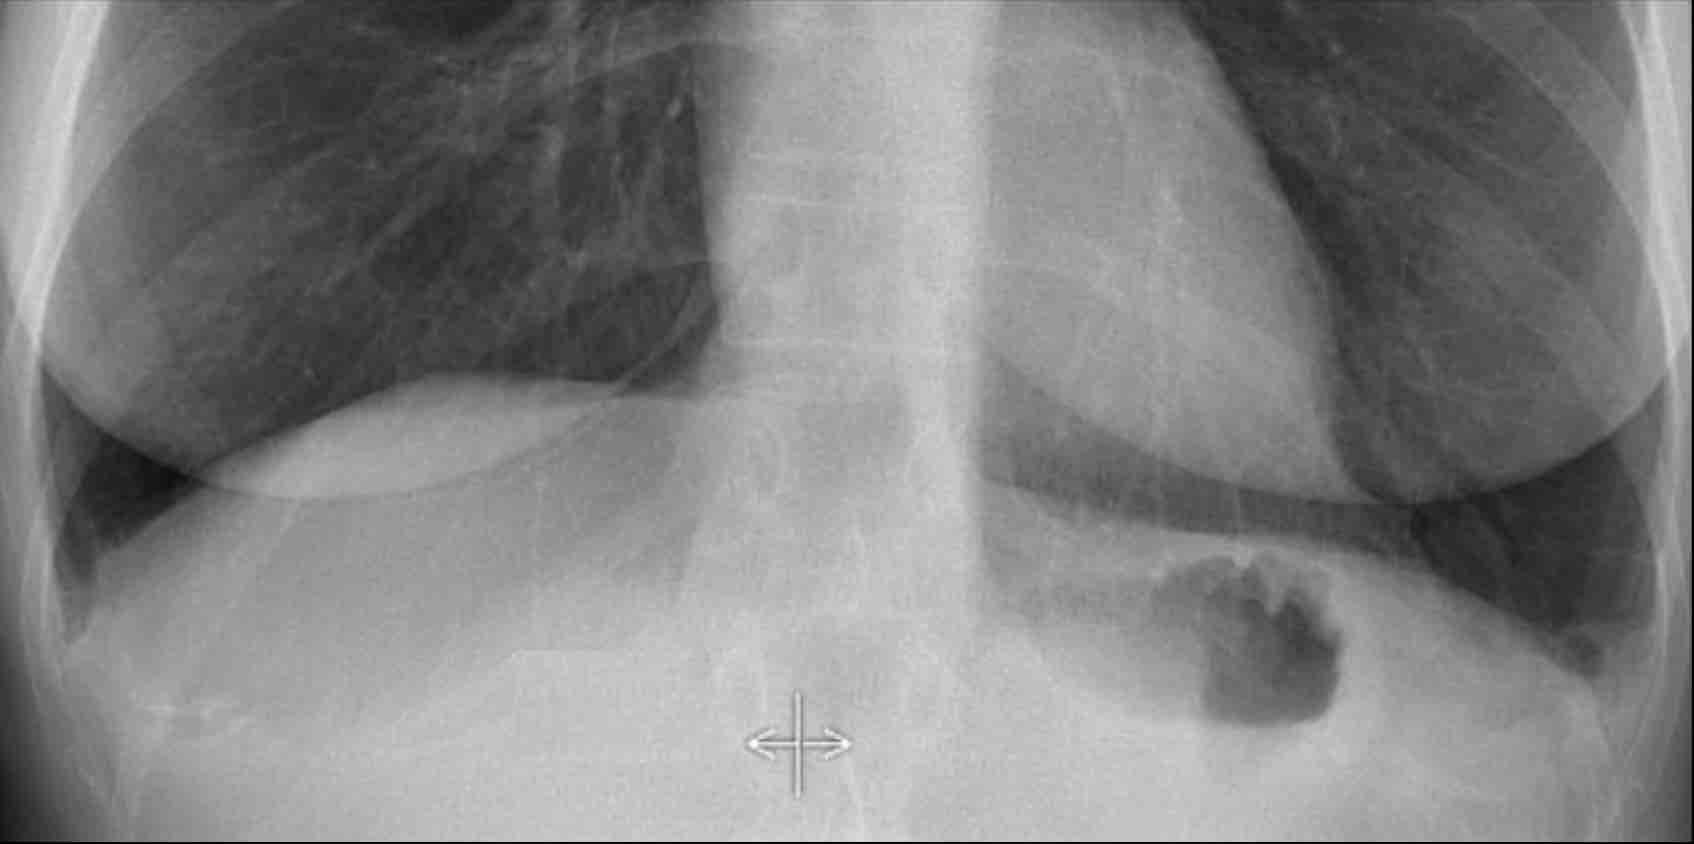

Vùng Khuất (2): Tổn thương Thùy Dưới Phải

Ví dụ này minh họa một khối lớn ở thùy dưới phải khó nhận biết trên phim PA nếu không chú ý kỹ đến các vùng khuất.

- Khi quan sát ban đầu, tổn thương không rõ ràng.

- Tuy nhiên, khi tập trung xem xét vùng dưới hoành và vùng sau tim, bất thường trở nên rõ ràng hơn.

- Phóng to hình ảnh để quan sát tốt hơn.